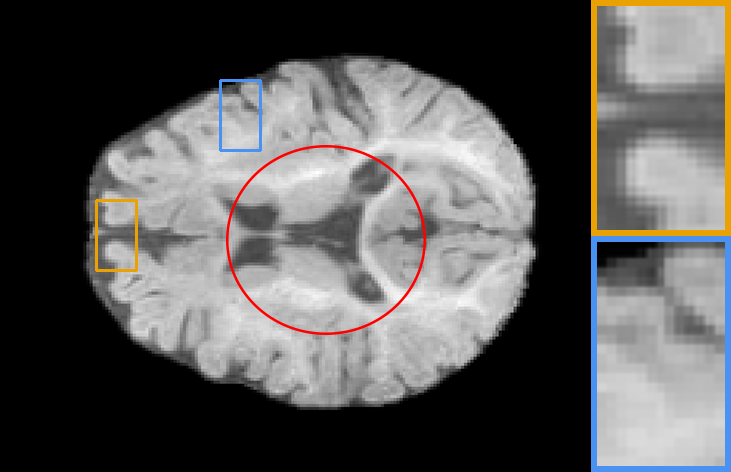

| Brain T1-to-T1 | Brain T2-to-T2 | Knee T1-to-T1 | Brain T2-to-T1 |

IV-C2 Automatic learning across registration tasks

To explore the influence of model weights, architectures, and training objectives in registration performance and verify the benefit from adaptive feature extraction cell, task-aware deformation estimation cell design, and scenario-oriented training objectives, we made groups of contrast experiments, covering diverse registration scenarios. Specifically, we first train a registration model on PPMI brain T1 MR image-to-atlas registration tasks, then take the model as initialization to adopt our auto-search strategy to register images of other different scenarios. The scenarios cover registration on another ADNI dataset, Brain T1-to-T1, Brain T2-to-T2, Knee T1-to-T1 and Brain T2-to-T1 setups.

In Table. II, we directly apply the model (with , , and ) on the PPMI dataset to other scenarios, corresponding to the 1st column result, showing poor performance. Whereas performances of re-trained models (with task-specific model weight ) on these tasks correspond to the 2nd column. We also demonstrate the performance of searched networks with auto-learned feature cells , deformation cells , and training objectives , corresponding to the 3rd to 5th columns. To fully capture the benefit of the proposed technique, we further report the increase in registration accuracy for cases where all hyperparameters are searched in the last column. We can observe that, firstly, retraining the model for different alignment tasks will result in better performance. Secondly, searched tailored architecture and training objectives largely improve numerical results, which means automatic learning combining training objectives, architectures and hyperparameters can achieves excellent alignment performance in different alignment scenarios.

Also, the models on the diagonal with a blue background perform second best which can be seen from Table. II, providing meaningful indications and conclusions. Firstly, when transferring to another dataset or image contrast, feature extraction plays a dominant role in model performance. Secondly, whereas transferring to another anatomical structure such as the knee data, regulating the deformation estimation section has a more significant impact on the performance of the model. Lastly, adjusting the training objective plays a more important role in the performance of a registration network when transferring to multi-modal datasets.